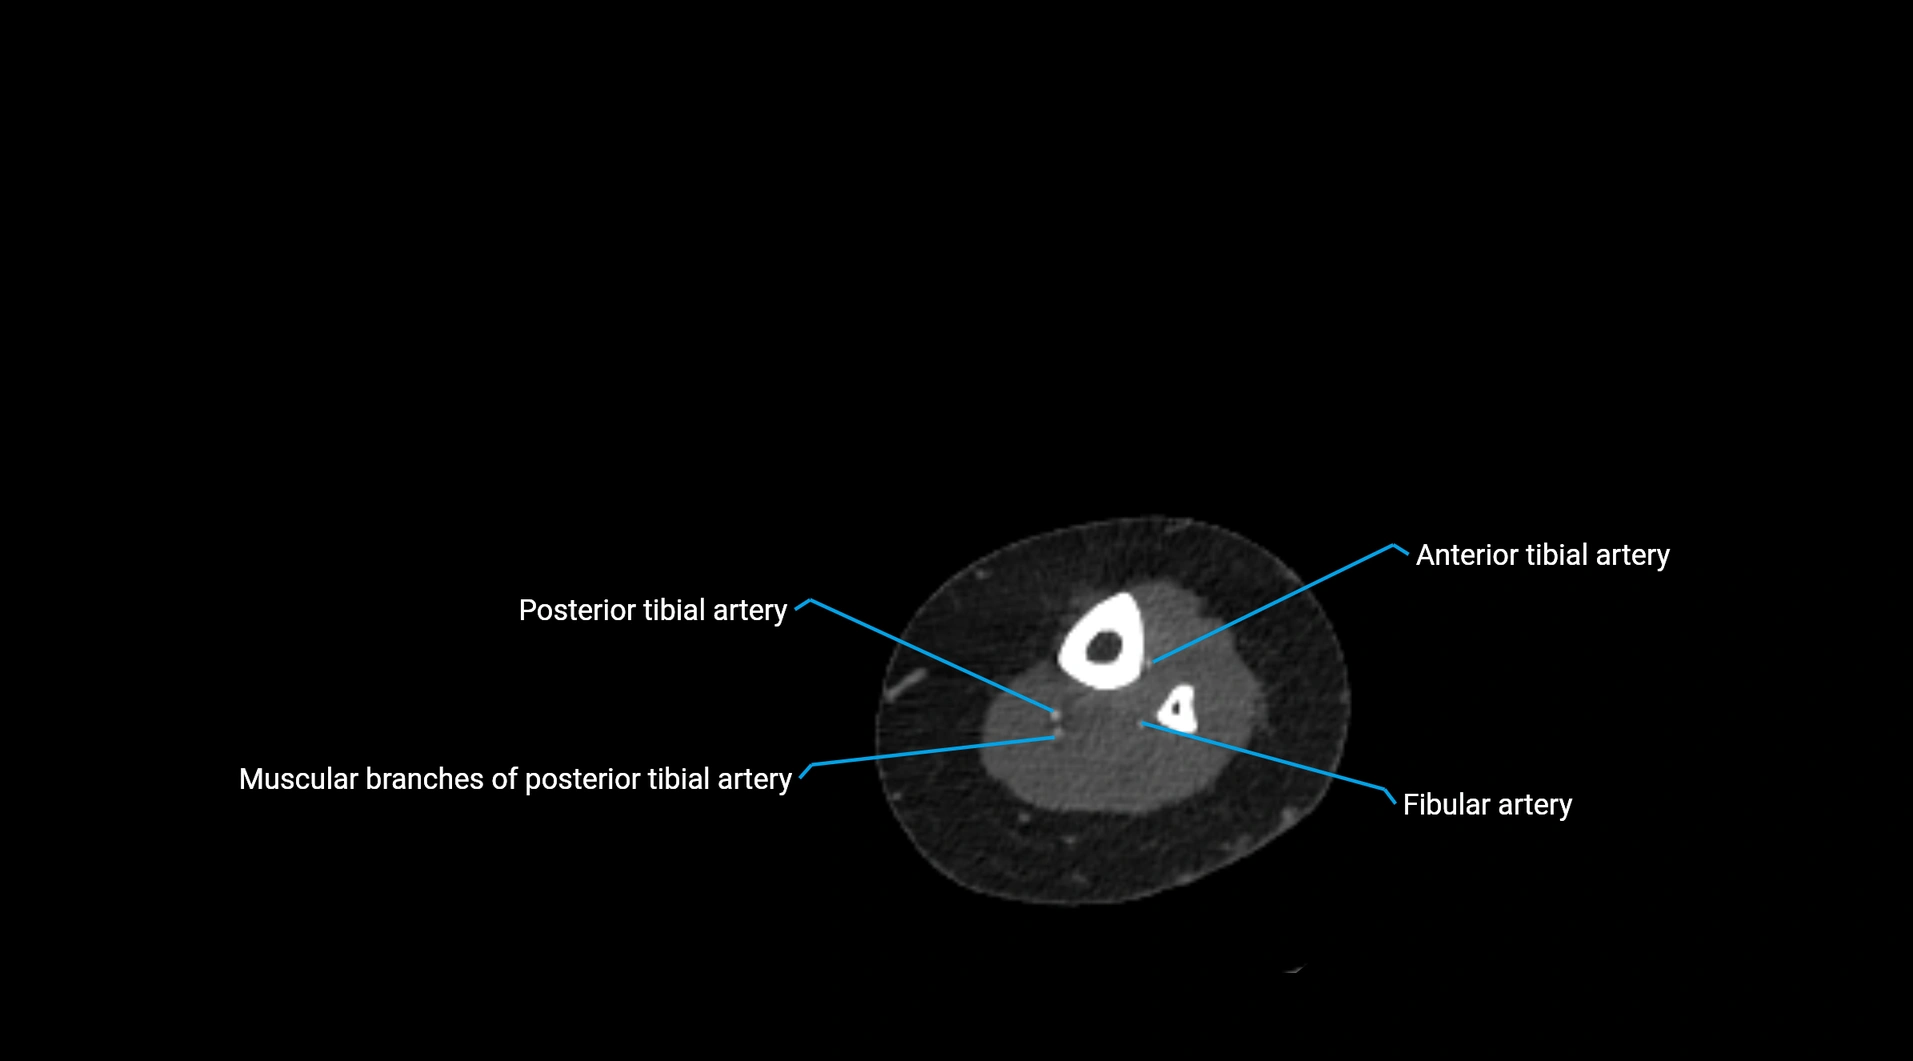

CT Appearance

Contrast-enhanced CT (CTA):

• Gold standard for abdominal aortic imaging

• Provides excellent detail of lumen, wall, aneurysm, thrombus, and branch vessels

• Multiplanar and 3D reconstructions help in aneurysm measurement, stent graft planning, and dissection evaluation

• Detects acute rupture, traumatic injury, or occlusion with high sensitivity